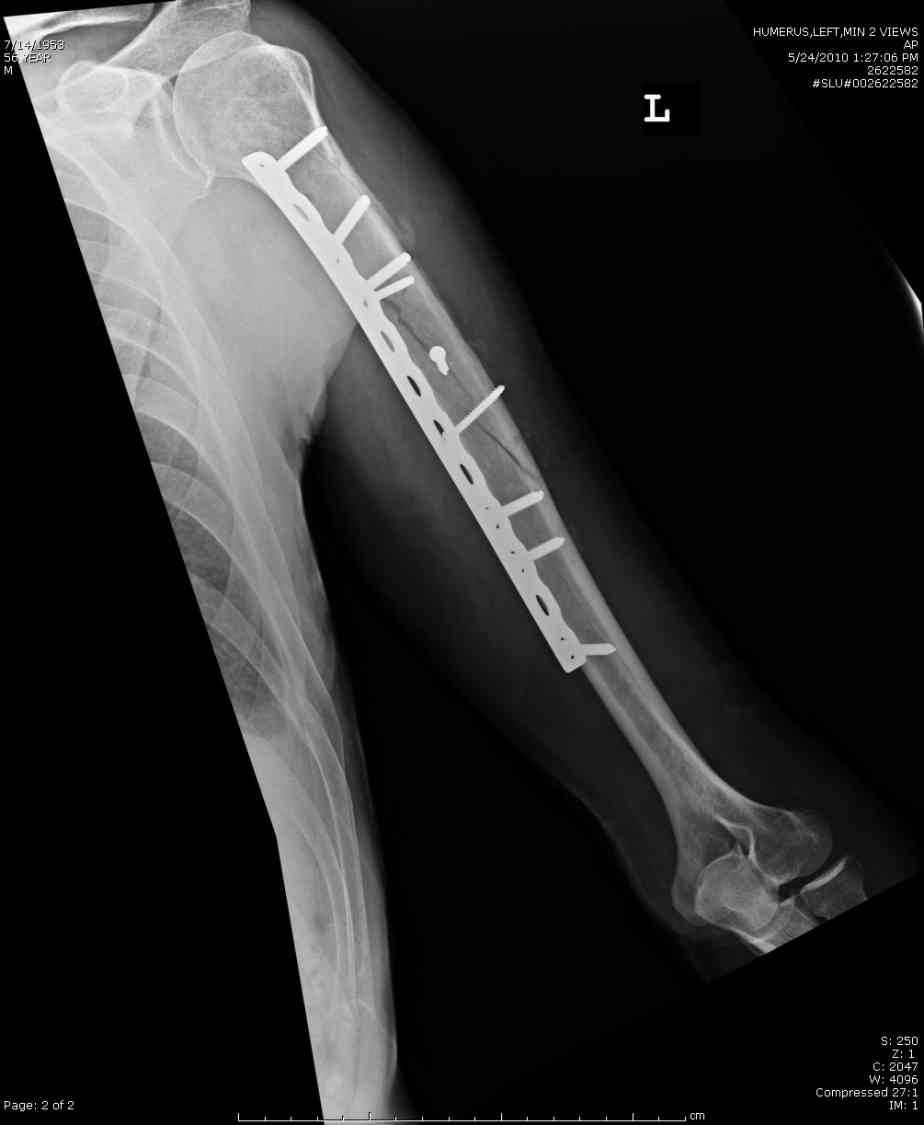

Кроме интрамедуллярного остеосинтеза, имеются другие варианты фиксации, наружный фиксатор и например здесь перелом плеча с повреждением нерва леченный открытым методом. Применен задний доступ с инспекцией нерва, межфрагментарная компрессия, фиксация узкой пластиной 4.5 мм.